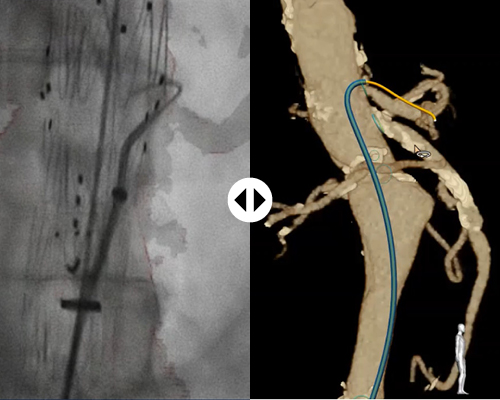

With FORS technology, clinicians can carry out parts of minimally-invasive interventions without the need for X- ray, which should minimize the risks associated with long-term radiation exposure.

Thanks to 3D Hub technology, you can continue to work with the catheters you’re already used to. The 3D Hub, in combination with FORS-enabled guidewires, enables your catheters to be visualized inside the body.

A four-core optical fiber is integrated into a guidewire. By sending light into this fiber and then analyzing how the light is reflected back along the length of the fiber, it becomes possible to calculate the shape as well as the perspective. In fact, you can ‘see’ the whole fiber, and thereby the guidewire (and a catheter slid over it). In real time. There is no need for additional external imaging technology; the device literally visualizes itself.

X-ray is still necessary to visualize the patient anatomy. FORS technology only visualizes devices. However, FORS has already been shown to reduce radiation exposure, for the patient and staff, during complex aortic procedures.